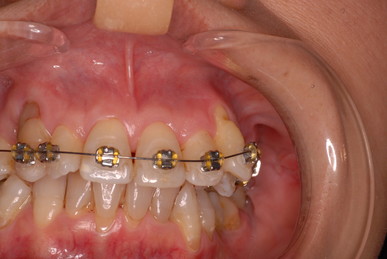

矯正治療一ヶ月後です。歯並びのガタガタはすぐよくなっています。

二ヶ月後ですが、歯周病が酷くなったので一時的に矯正治療を中止しました。歯周ポケットの深さを測っています。

挿入したゴムのポイントです。

歯並びは綺麗になり掃除はしやすくなったはずですが、矯正治療中は

磨きにくいので歯周病や虫歯が酷くなりやすいのです。